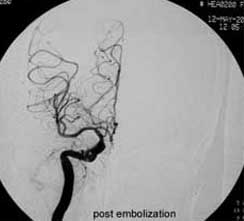

血管内栓塞对于单支或少数供血动脉的AVM,特别是新近出血的病例,可以达到微侵袭、痛苦小、疗效迅速的目的。

近来改变栓塞方式,将导管直接放置 畸形血管团内,注射NBCA胶,可使畸形团的解剖 治愈率提高至27%。再加上更细、超滑的微导管问世,栓塞的并发症更为降低。针对大型、功能区 的AVM栓 塞可缩小其体积,改善血液动力学分布,以利于显微外科技术切除或放射外科治疗,是后二者的重要辅助手段。